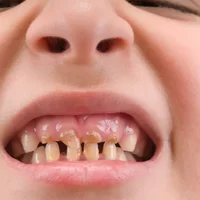

Caries dentaires chez les enfants

Bouche et dents